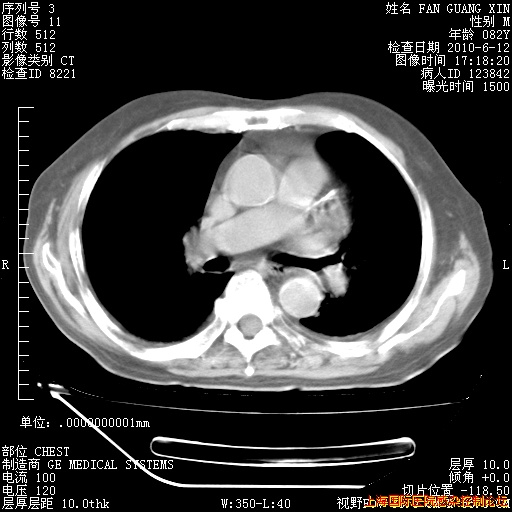

补发6月12日肺部CT肺窗

6月12日肺窗